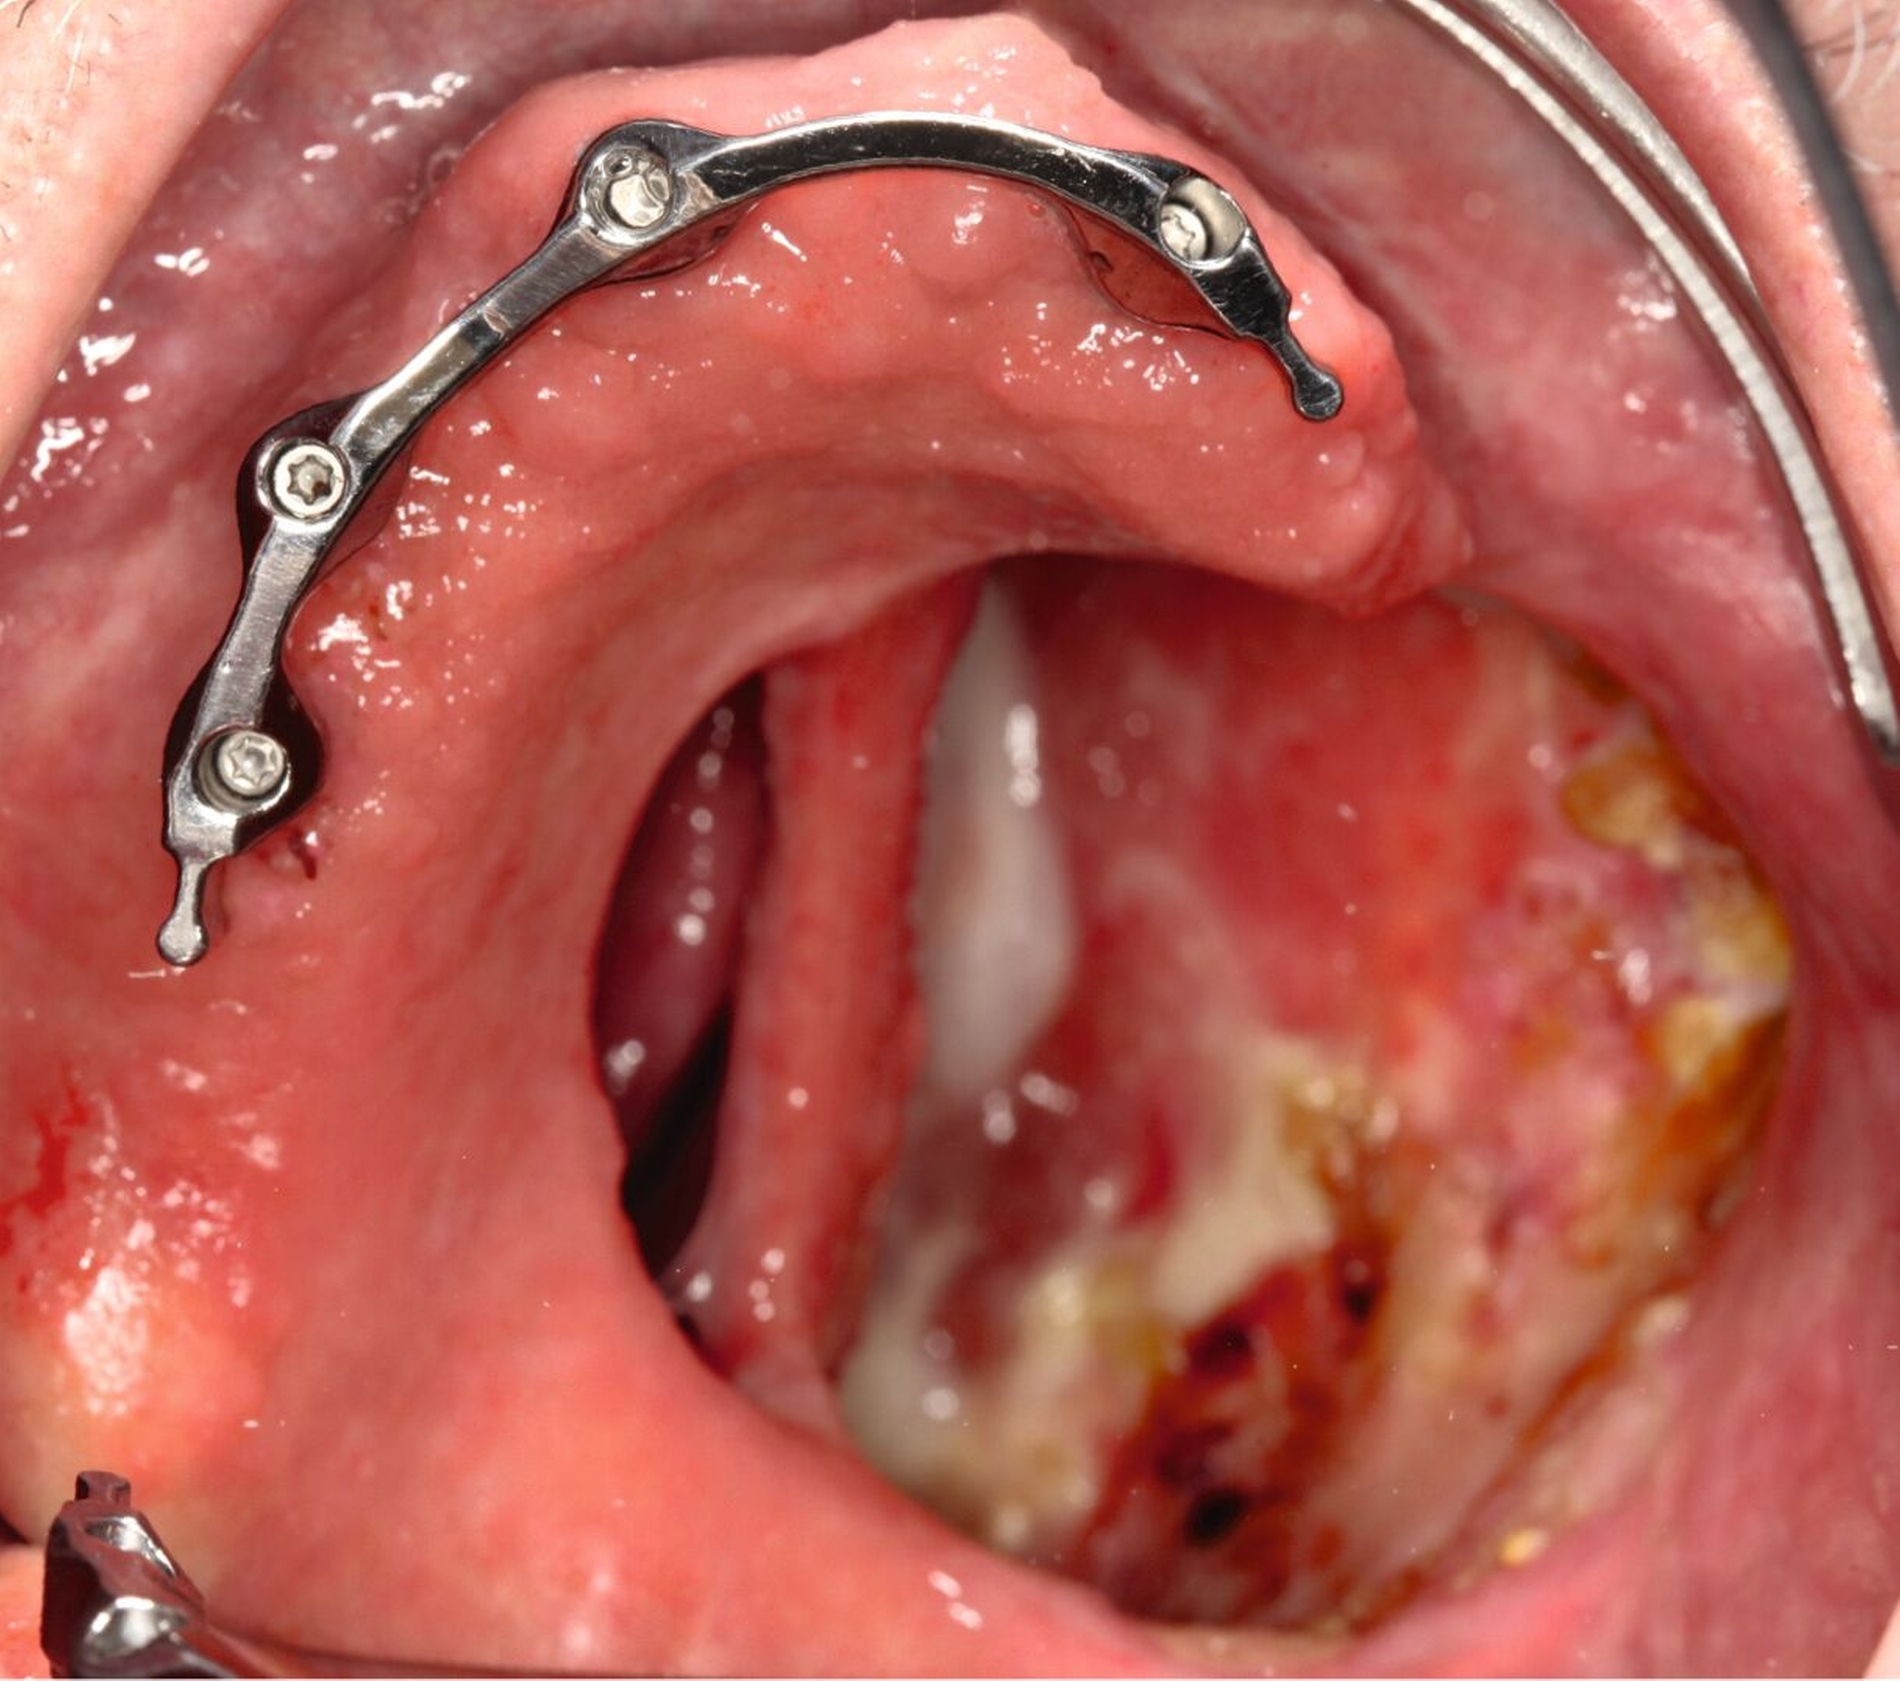

Bei einer Obturator-Prothese (Abbildung 2) erfolgt der Defektverschluss mittels hartem Acrylat-Prothesenkunststoff. Sie kann im Zenit offen oder geschlossen gestaltet sein. Der Halt wird über Klammern, Teleskope oder eine implantatgetragene Verankerung erzielt. Bei vollständiger Zahnlosigkeit ist eine Obturator-Prothese nicht zu empfehlen, da der gewöhnlich genutzte Saugeffekt nicht hergestellt werden kann. Bei zahnlosen Patienten, die keine Implantate erhalten können oder sollen, ist es sogar empfehlenswert, den Defekt nicht zu rekonstruieren, damit Unterschnitte für einen Silikon-Obturator genutzt werden können.

Mit Einbringen eines Wendel-Tubus zur Sicherung der Atemwege, lässt sich der Defekt ohne Probleme abformen (Abbildung 3). Jener verhindert auch, dass der spätere Silikon-Obturator die Atemwege nicht verlegt. Speziell visköses Silikon-Abformmaterial („Laborsilikon Orange“, 12 Shore A, Institut für Anaplastologie Schilling, Würzburg, Deutschland) verhindert ebenfalls, dass die Abformmasse in Richtung des Pharynx fließt. Nach der Defektabformung können die herkömmlichen Arbeitsschritte für einen Zahnersatz (als Zusatz zum Silikon-Obturator oder zur Herstellung einer Obturator-Prothese) erfolgen.